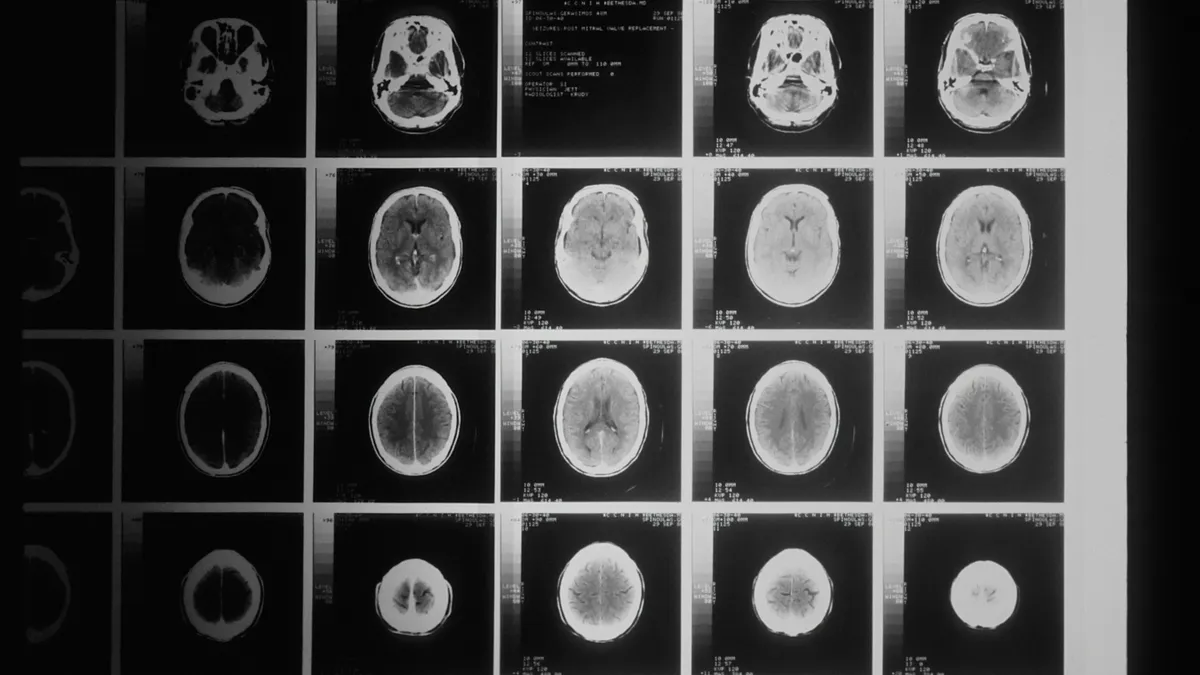

„Azt mondták, menopauza – most közölték: hat évem maradt hátra”

Évei lehetnek hátra. Az édesanya nagyon fél.